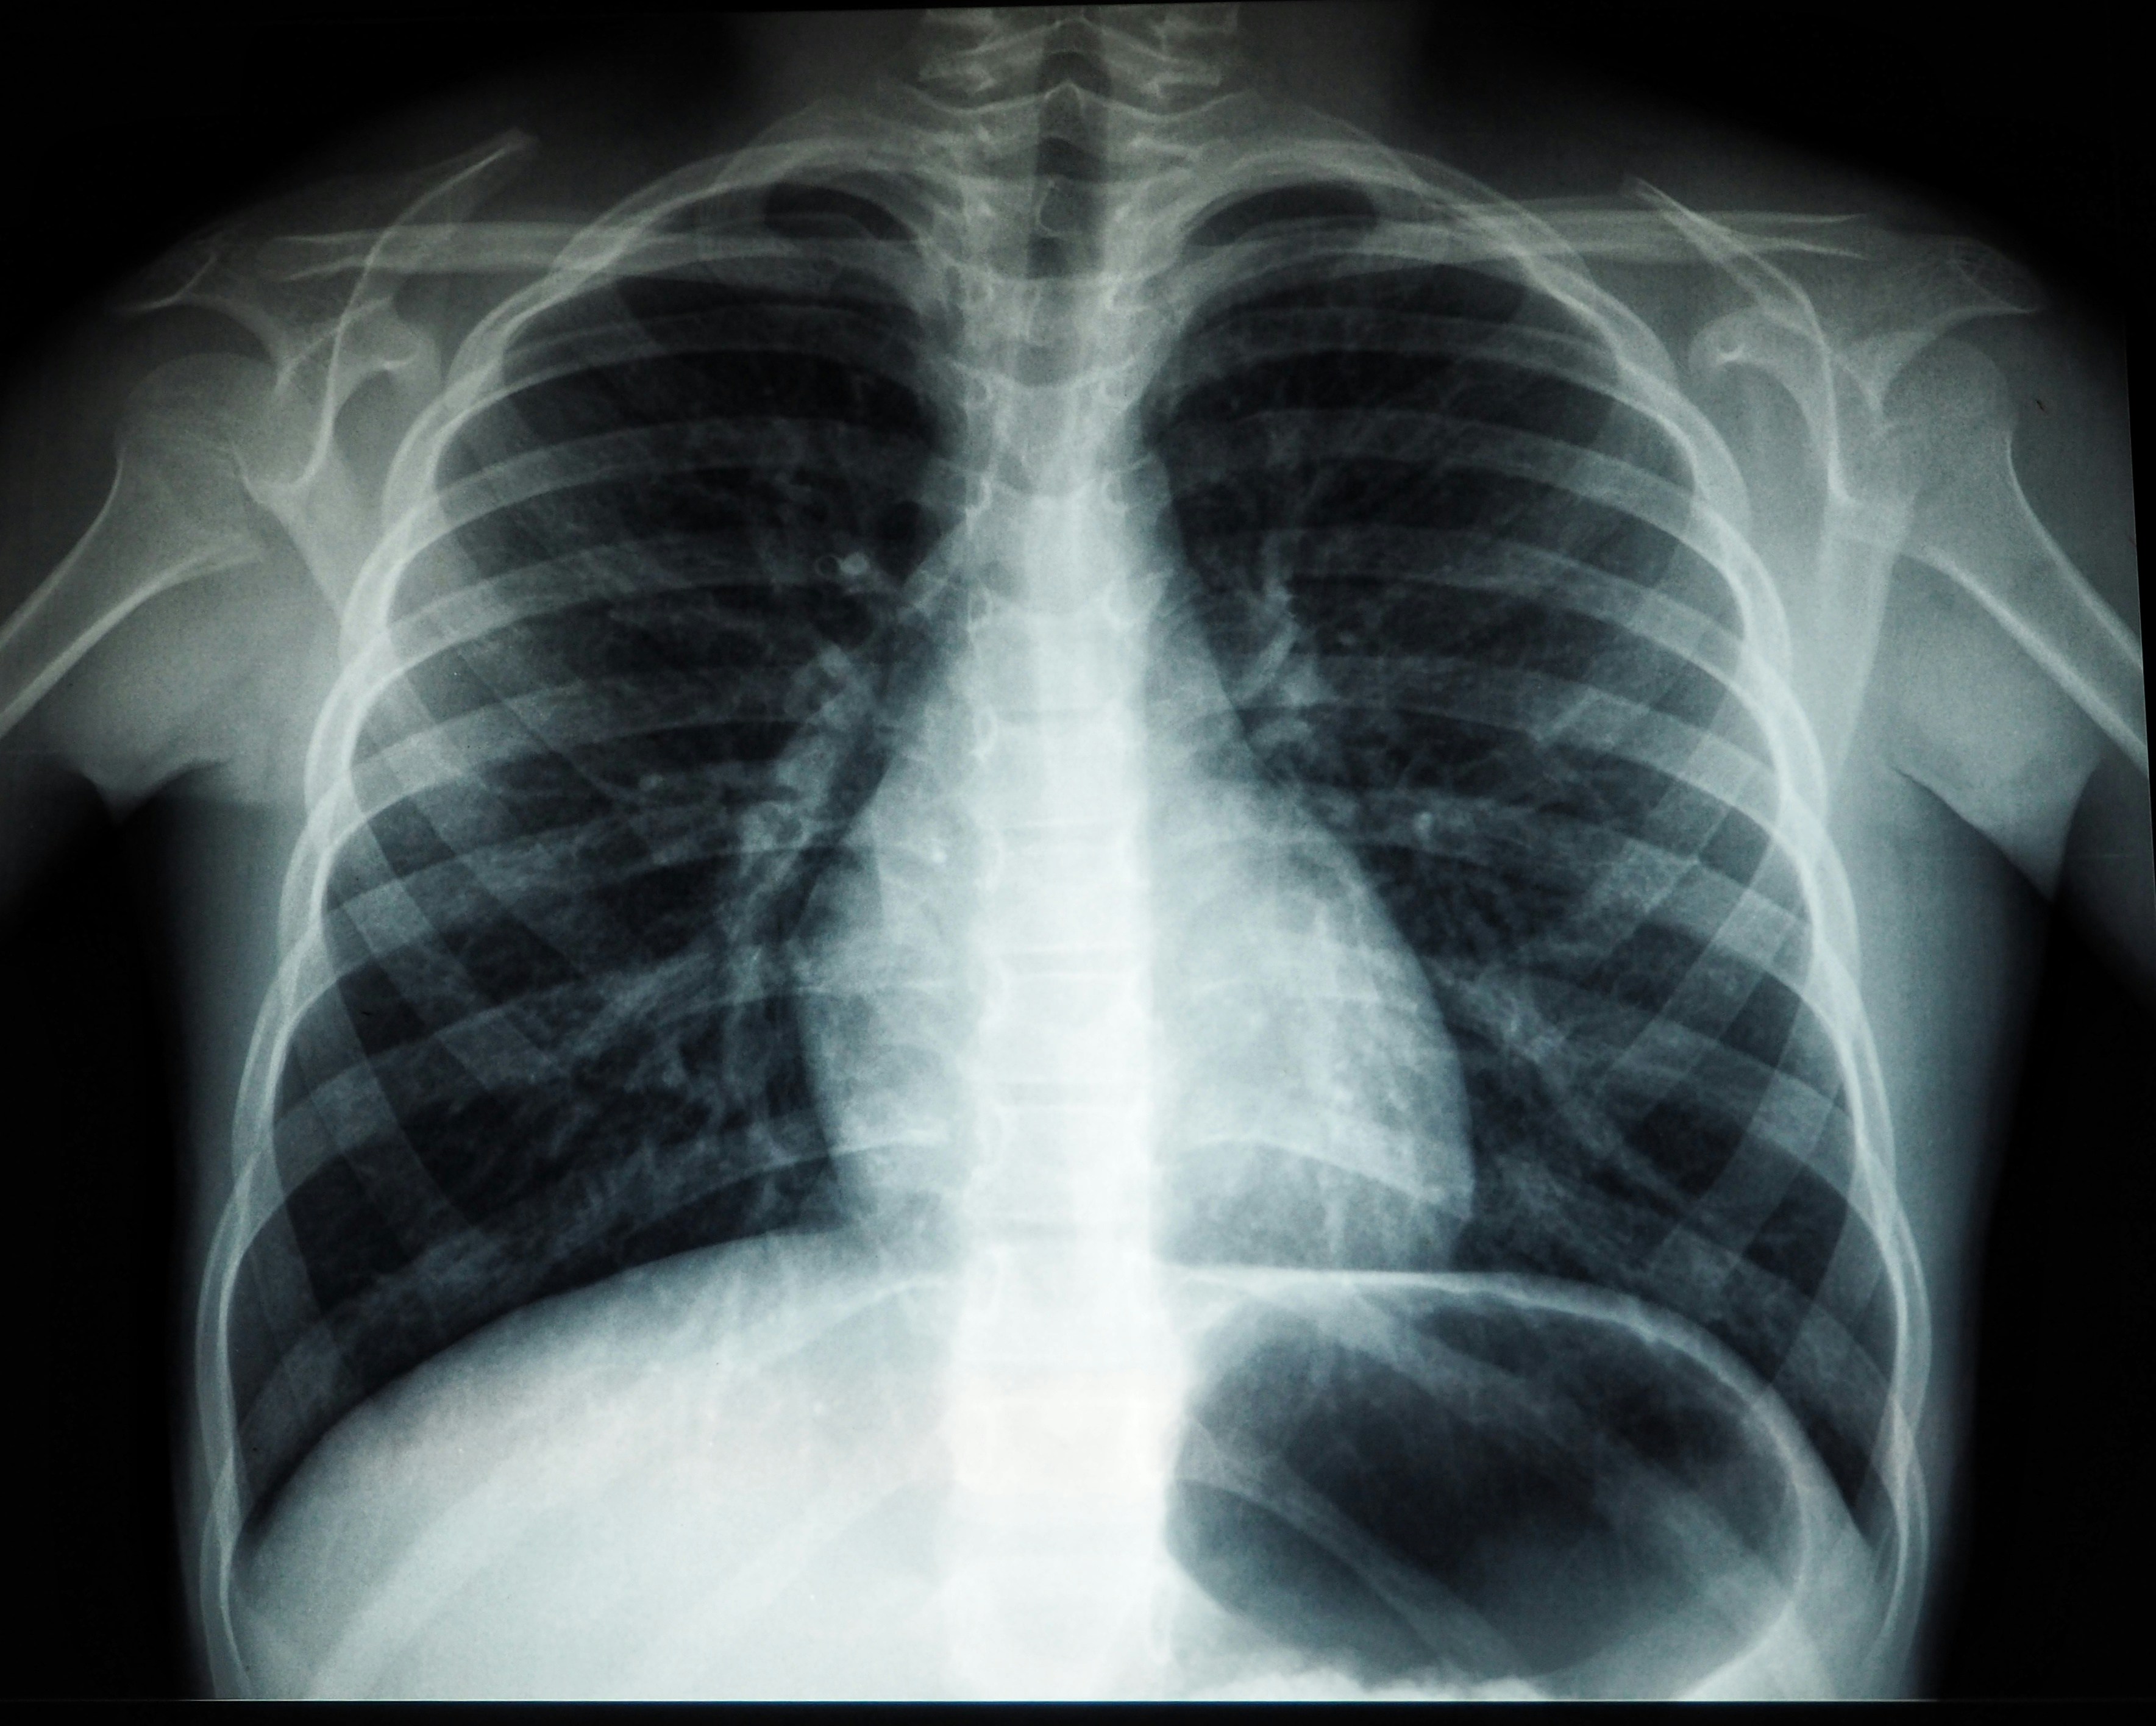

Tórax Simple

Radiografía básica de la caja torácica

RX

Tórax PA y Lateral

Evaluación completa del tórax en dos proyecciones

Radiografía de tórax de alta definición realizada con equipos digitales

Radiología

Radiología digital completa

Más de 40 tipos de radiografías disponibles: tórax, columna, extremidades, cráneo y más. Resultados digitales y placa física entregados el mismo día.